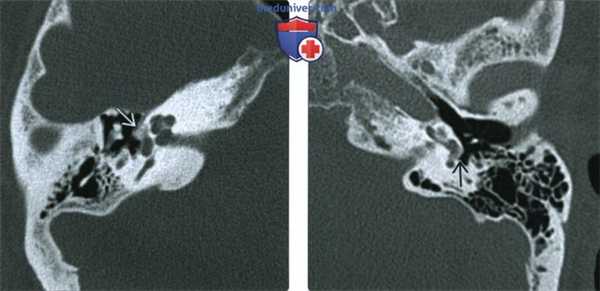

(Слева) При аксиальной КТ левой височной кости визуализируются типичные литические бляшки (сочетанный фенестральный и кохлеарный отосклероз). Пациенту была выполнена стапедэктомия с протезированием стремечка. Обратите внимание на протез стремечка с плотностью металла.

(Справа) При аксиальной МРТ Т1ВИ С+ FS у этого же пациента определяется контрастное усиление спереди от овального окна (щель перед окном) и вокруг улитки (фенестральный и кохлеарный отосклероз, соответственно).

3. МРТ при отосклерозе:

• Т2 ВИ:

о Тонкосрезовая МРТ Т2 высокого разрешения: отосклероз (даже распространенный) может не определяться

о В больших бляшках может обнаруживаться легкое повышение интенсивности сигнала

• Т1 ВИ С+:

о Контрастирующиеся точечные очаги в медиальной стенке среднего уха (ФОто) ± перикохлеарные очаги в костном лабиринте (КОто):

- Наиболее очевидны при сочетании ФОто и КОто

о В тяжелых случаях контрастирующиеся участки могут обнаруживаться повсюду в костном лабиринте